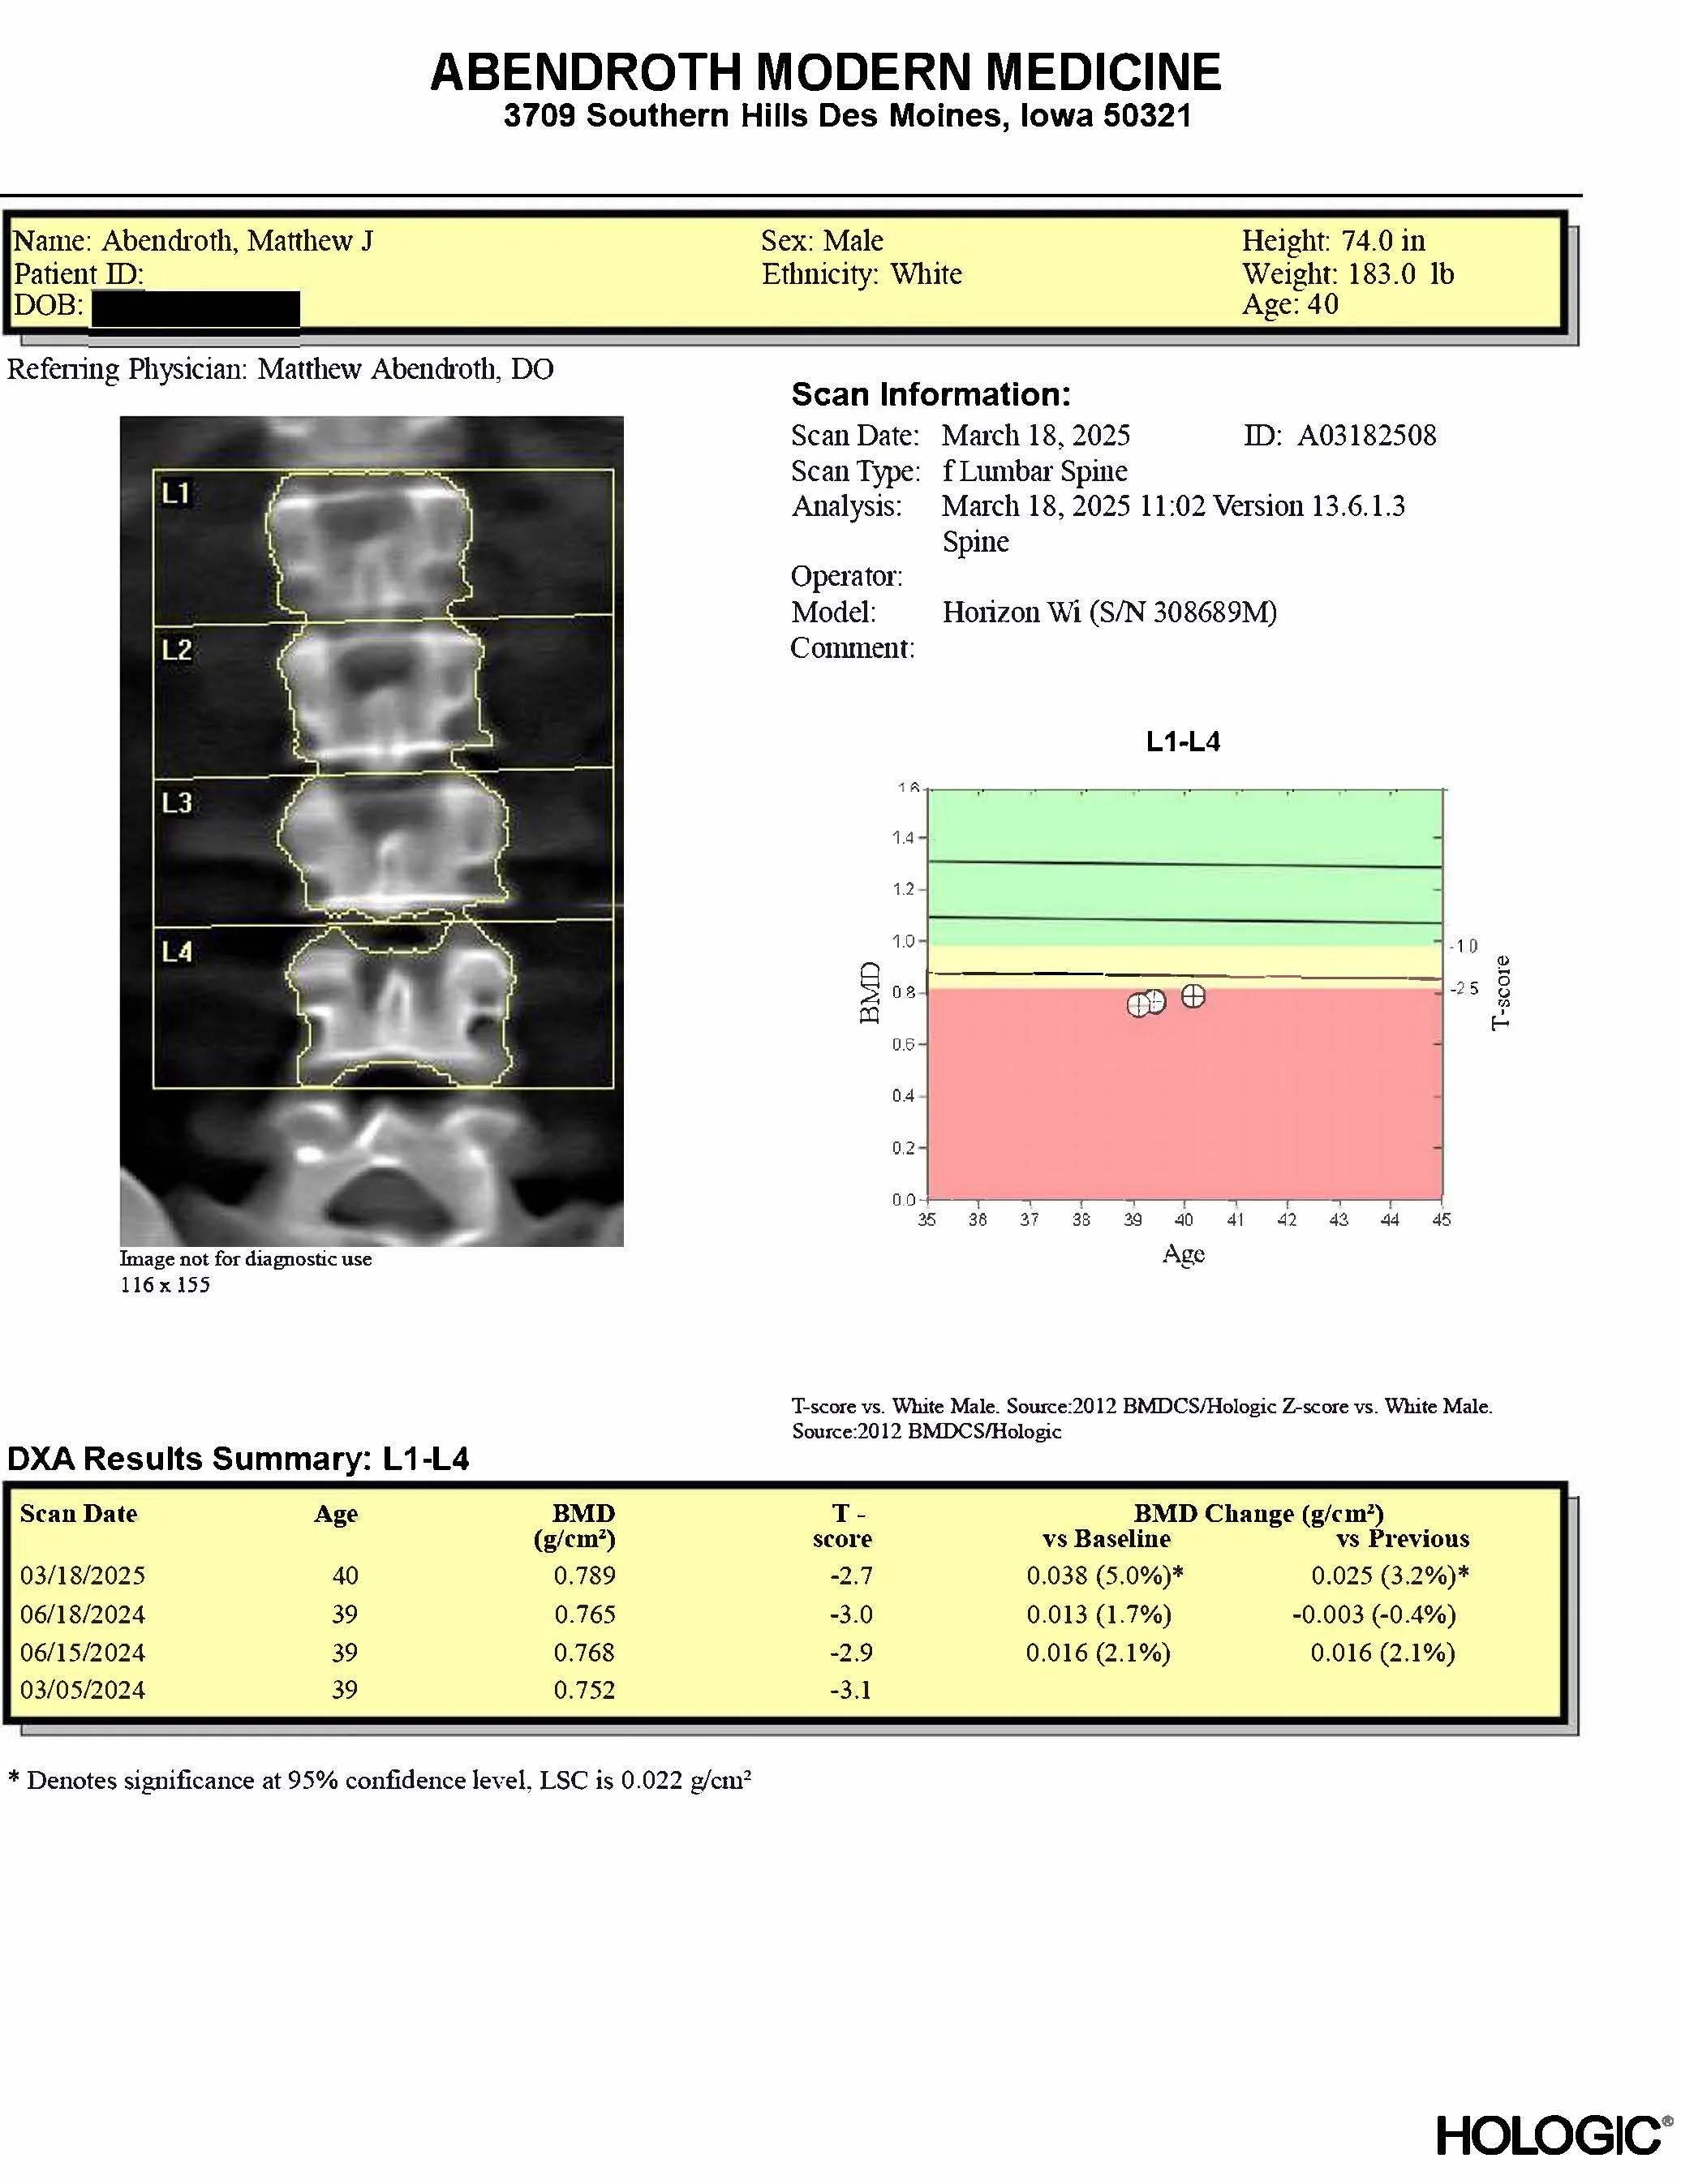

This is my actual bone density scan

MY OWN OSTEOPOROSIS

When I bought the DEXA scanner I would need for this clinic, naturally, the first thing I did was check my own bone density. To my surprise, I discovered that I had osteoporosis, or very low bone mineral density. This is thought to be extremely unusual in a young man, but I have diagnosed it in another man in his 30’s, and have diagnosed osteopenia — the same thing, but less severe — in many other young men and women in their 30’s and 40’s. In the traditional medical model, none of us would have known for decades, while our bones continued to silently weaken. We would find out when a bone broke from minor trauma, or when guidelines said we should be screened — at age 65 to 75, after much more bone had been lost.

Because I found out, I have been able to discover the cause of my osteoporosis and treat it using a multi-pronged approach, and have reversed my osteoporosis, as I have done for my patients.